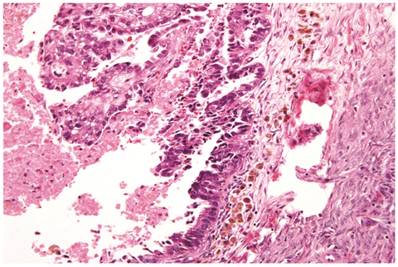

The clinicopathologic features with respect to age, stage, bilaterality, tumor size, gross appearance, and distributions of grade and architectural pattern are shown in Table 4. Between cases, the CAs histologically displayed combinations of tubulocystic (Fig. 3A), papillary, and solid architectural patterns; hobnail, polygonal, and flat cell shapes (Fig. 3B); clear or oxyphilic cytoplasm; a spectrum of atypia ranging from mild to severe; generally low mitotic indices; and hyalinized stroma, similar to the features seen in ovarian clear cell CAs described in detail elsewhere.13,47,70,75,77

Figure 3

Carcinoma with adenofibromatous background. The carcinoma component exhibits a (A) tubulocystic pattern with (B) oxyphilic, hobnail, and flat atypical cells. (C) The adenofibromatous component does not show architectural features of clear cell carcinoma or notable atypia.

The background of the tumor contained variable amounts of adenofibromatous components (Fig. 3C). The proportion of the clear cell CA component in the tumors ranged from focal to diffuse, but cases with focal CA components exceeded conventional definitions for microinvasion (>3 mm in greatest dimension). Notable nuclear atypia was focally present in the adenofibromatous background in 34 (24%) cases, and the histologic appearance of such foci was similar to those with notable atypia in APTs described above. A comparison with non-adenofibromatous clear cell CAs is shown in Table 4.